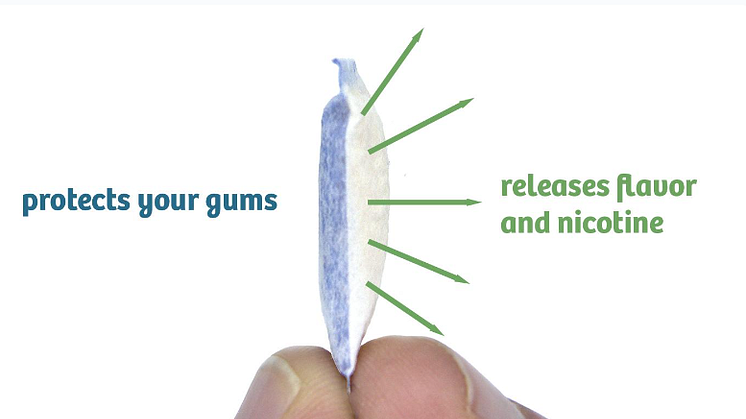

This inspired Wiberg to patent the idea. However, every brand he approached with his idea rejected it, with the reason given for the rejections often being “it’s supposed to sting.” Hence he decided to set up his own company, and the result is Stingfree products, which come with an impermeable barrier on the gum side of the pouch, preventing the familiar burning and stinging sensation of these types of products. Wiberg, along with his son Daniel, now market these premium pouches through their company, Sting Free AB. Their goal is for this technology to be adopted by all manufacturers of snus and NPs to benefit users worldwide.